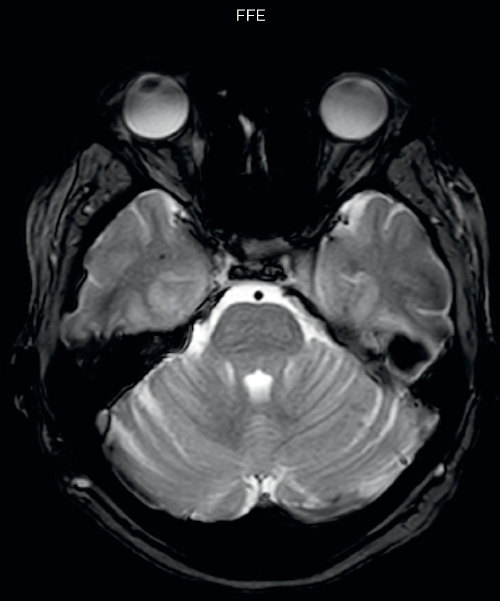

Hemosiderin foci in brain

Gradient echo imaging and SWIp are compared in a patient with radiation-induced foci of hemosiderin deposition. A greater number of small foci is seen on the SWIp image. Ingenia 3.0T

SWIp in patients with hypertension, amyloid angiopathy, trauma

The SWIp sequence offers high resolution 3D susceptibility weighted brain imaging, which helps to visualize deoxygenated blood or calcium deposits. In combination with other clinical information, it may help in the diagnosis of various neurological pathologies

Neuroradiologist Joshua Nickerson, MD, discusses their findings in comparing SWIp versus T2* weighted imaging in different types of patients.

“With SWIp we are basically looking for blood byproducts. It is a sensitive method for visualizing small lesions containing deoxygenated blood. In our comparison, SWIp images are vastly better than gradient echo imaging, there’s no question of that anymore.”

“We find the SWIp images very useful in three areas in particular. In patients with a history of hypertension, it offers clear visualization of hemosiderin deposition from hypertensive hemorrhages. We certainly see a greater number of foci of hemosiderin deposition on the SWIp images than on the T2* gradient echo images. In addition, it also helps us visualize amyloid depositions in patients with amyloid angiopathy.”

Dr. Nickerson mentions trauma patients are the third large area where SWIp is useful. “We benefit from SWIp in trauma patients, certainly in cases with diffuse axonal injury and shearing injuries. Our study shows that SWIp usually provides us better visualization,” he says.

“Apart from these three, SWIp also helps us to beautifully depict the normal venous anatomy in patients with venous outflow issues or vascular congestion. In some cases, we have seen downstream effects of arterial problems. And in patients with vascular malformations we have seen deposition of blood products associated with those.”